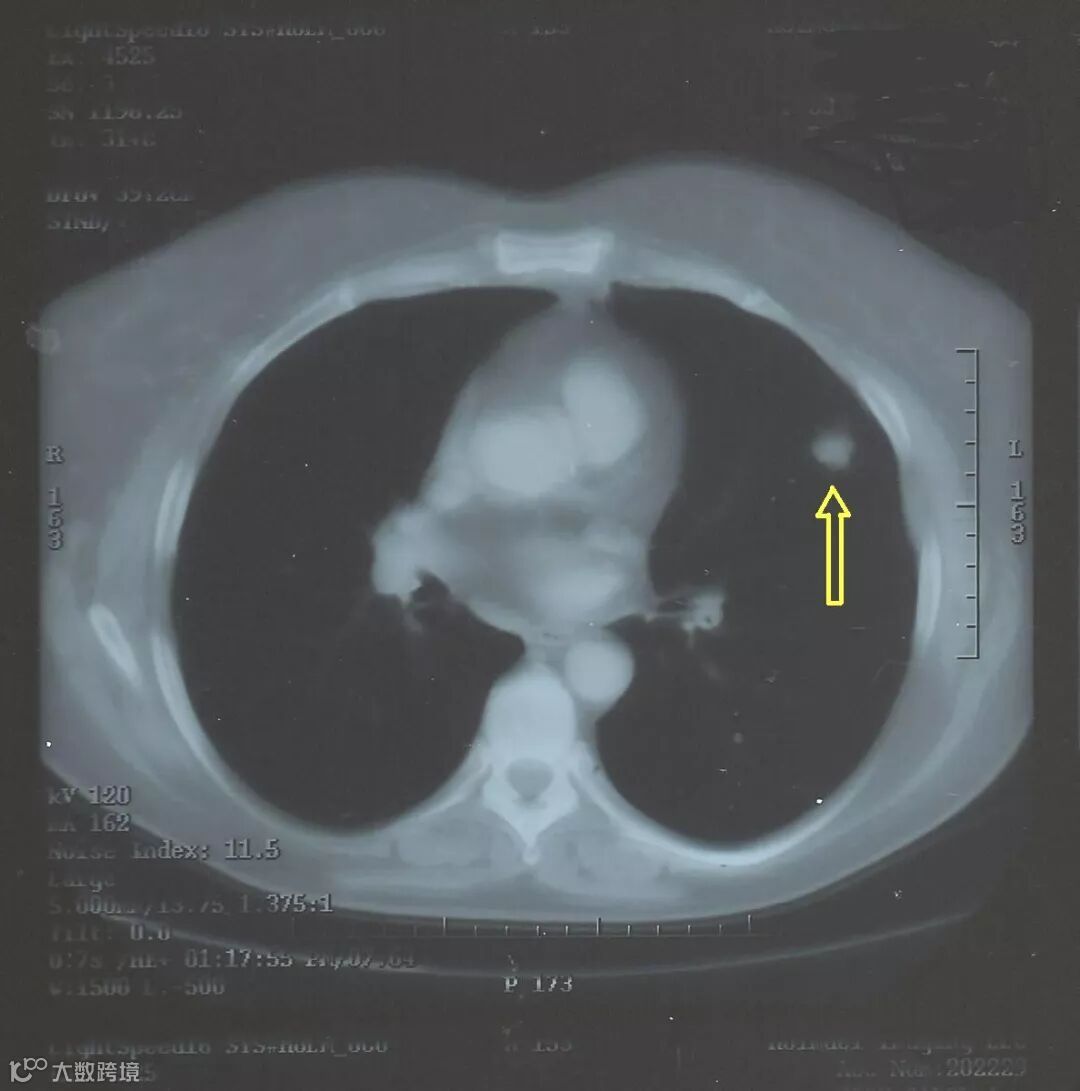

通常,下一步是复查CT,以了解结节是否随时间增长。两次检查的时间间隔可能从一个月左右到一年不等,具体取决于医生认为结节是癌症的可能性有多大。这是基于结节的大小、形状和位置,以及它的外表特征。肺结节的大小通常为约5毫米至30毫米。较大的肺结节发生癌变可能性比较大,30毫米以上的,肺癌可能性更大,一般就不叫肺结节了,而是叫做肺肿块。

如果结节大小、形状或外观在两年内没有改变,那么它是非癌性的可能就比较大。而如果第二次扫描显示结节已经明显变大,或者结节有其他相关特征,那么医生需要获取这个结节的样本,以检查其是否有癌细胞。这被称为活组织检查,简称活检。这可以通过不同方式完成: